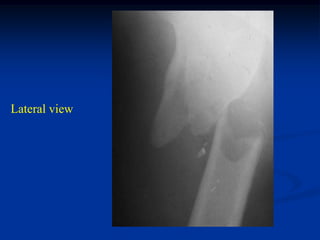

Case #1143.1

55 year male with

subtroch path fracture

2nd to metastatic lung CA

Lateral view